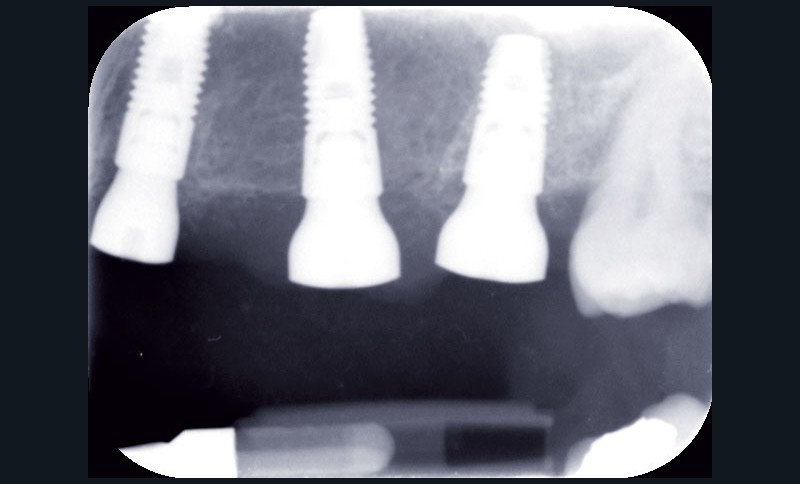

Au maxillaire, 3 implants Astra Tech Implant EV (Dentsply) sont posés en un temps chirurgical. Une empreinte pick-up sera réalisée après 4 mois de cicatrisation.